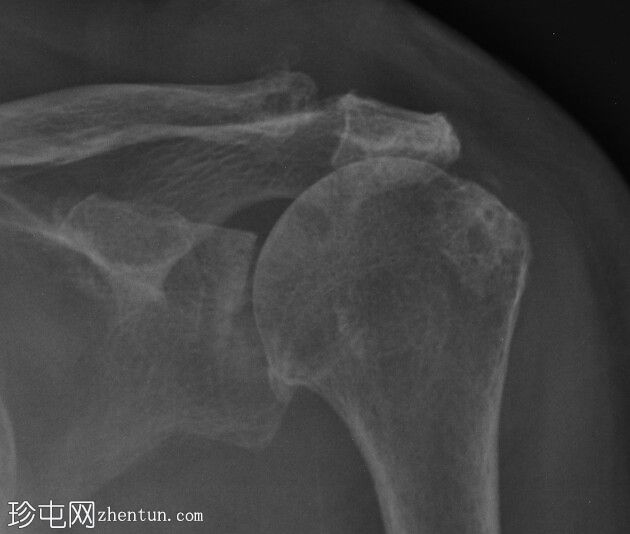

正位片

(站立位)

站立位肩关节X线片最显著的发现是肱骨头近端移位,导致肩峰间隙变窄。其他发现包括:肱骨头大结节软骨下硬化和囊肿、肱骨头关节面软骨下囊肿、肩胛骨肩峰下表面软骨下硬化、肩胛盂上间隙变窄,以及锁骨外端颅侧小骨形成。左侧肩锁关节区域软组织肿胀,临床上可见肿块。未见骨折/脱位/骨损伤。